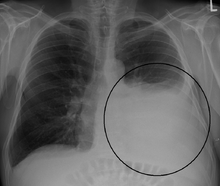

A pleural effusion appears as an area of whiteness on a standard posteroanterior chest X-ray.[5] Normally, the space between the visceral pleura and the parietal pleura cannot be seen. A pleural effusion infiltrates the space between these layers. Because the pleural effusion has a density similar to water, it can be seen on radiographs. Since the effusion has greater density than the rest of the lung, it gravitates towards the lower portions of the pleural cavity. The pleural effusion behaves according to basic fluid dynamics, conforming to the shape of pleural space, which is determined by the lung and chest wall. If the pleural space contains both air and fluid, then an air-fluid level that is horizontal will be present, instead of conforming to the lung space.[6] Chest radiographs in the lateral decubitus position (with the patient lying on the side of the pleural effusion) are more sensitive and can detect as little as 50 mL of fluid. At least 300 mL of fluid must be present before upright chest X-rays can detect a pleural effusion (e.g., blunted costophrenic angles).

Massive left-sided pleural effusion (whiteness) in a patient presenting with lung cancer.